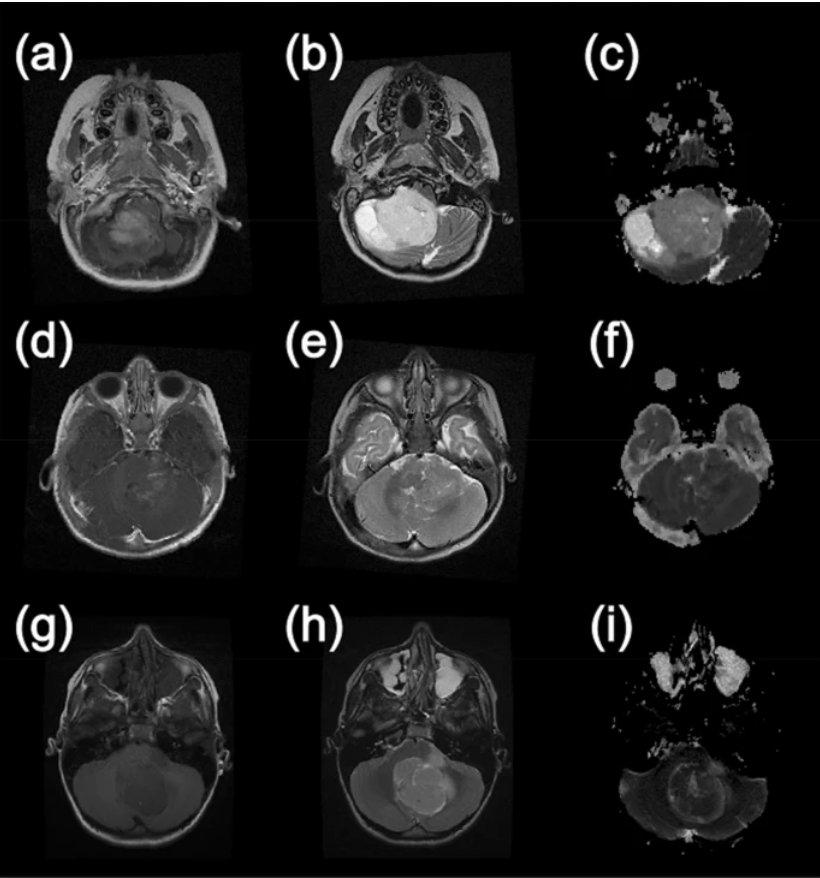

Example MR images from paediatric brain tumour patients. This first column shows T1-weighted images following the injection of gadolinium contrast agent. The second column shows T2-weighted images and the final column shows apparent diffusion coefficient maps calculated from diffusion-weighted images. (a–c) are taken from a patient with a Pilocytic Astrocytoma, (d–f) are from a patient with an Ependymoma and (g–i) were acquired from a patient with a Medulloblastoma. Image courtesy of Nature Research Journal

Diffusion weighted imaging involves the use of specific advanced MRI sequences, as well as software that generates images from the resulting data that uses the diffusion of water molecules to generate contrast in MR image. One can then extract an Apparent Diffusion Coefficient (ADC) map, analysed values of which can be used to tell you more about the tumor.

The study involved 117 patients from five primary treatment centers across the UK with scans from twelve different hospitals on a total of eighteen different scanners, the images from them were then analysed and region of interests were drawn by both an experienced radiologist and an expert scientist in paediatric neuroimaging. Values from the analysis of Apparent Diffusion Coeffcient maps from these images' regions have been fed to AI algorithms to successfully discriminate the three most common types of pediatric posterior fossa brain tumours, non-invasively.